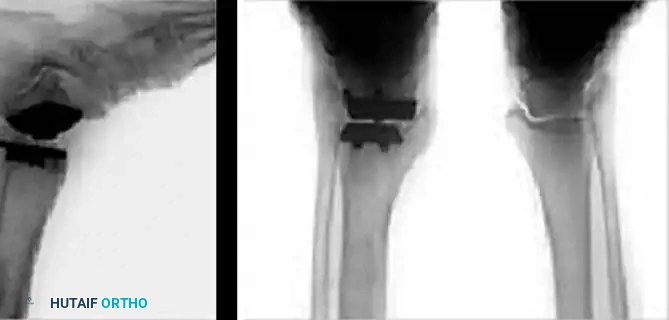

SCANDINAVIAN TOTAL ANKLE REPLACEMENT (STAR)

The Scandinavian Total Ankle Replacement (STAR) represents a fundamental shift in TAA philosophy. It is a mobile-bearing, three-component design consisting of a cementless tibial flat plate, a highly polished talar component, and a freely mobile UHMWPE meniscus interposed between them.

Kinematic Decoupling:

The mobile polyethylene component allows for minimal constraint at the flat tibial interface. This unconstrained articulation effectively decouples rotational and translational forces, drastically reducing stress transfer to the tibial bone-prosthesis interface—a primary cause of aseptic loosening in fixed-bearing designs.

Conversely, the inferior surface of the polyethylene is highly conforming to the central ridge of the talar component. This high conformity maximizes contact area, theoretically reducing contact stresses and minimizing superior-to-inferior polyethylene wear.

Implantation of the STAR prosthesis is highly bone-conserving compared to the Agility system.

2. Bone Resection: The talar cuts are minimal, preserving the structural integrity of the talar neck and body. The system does require resurfacing of the medial and lateral talar facets to accommodate the highly conforming talar component.